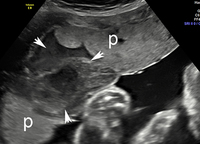

Descolamento da placenta

Imagem de ultrassonografia de descolamento da placenta: a placenta normal está marcada com 'p'; área de descolamento indicada por setas brancas

Do acervo de Dr Y Oyelese; usado com permissão